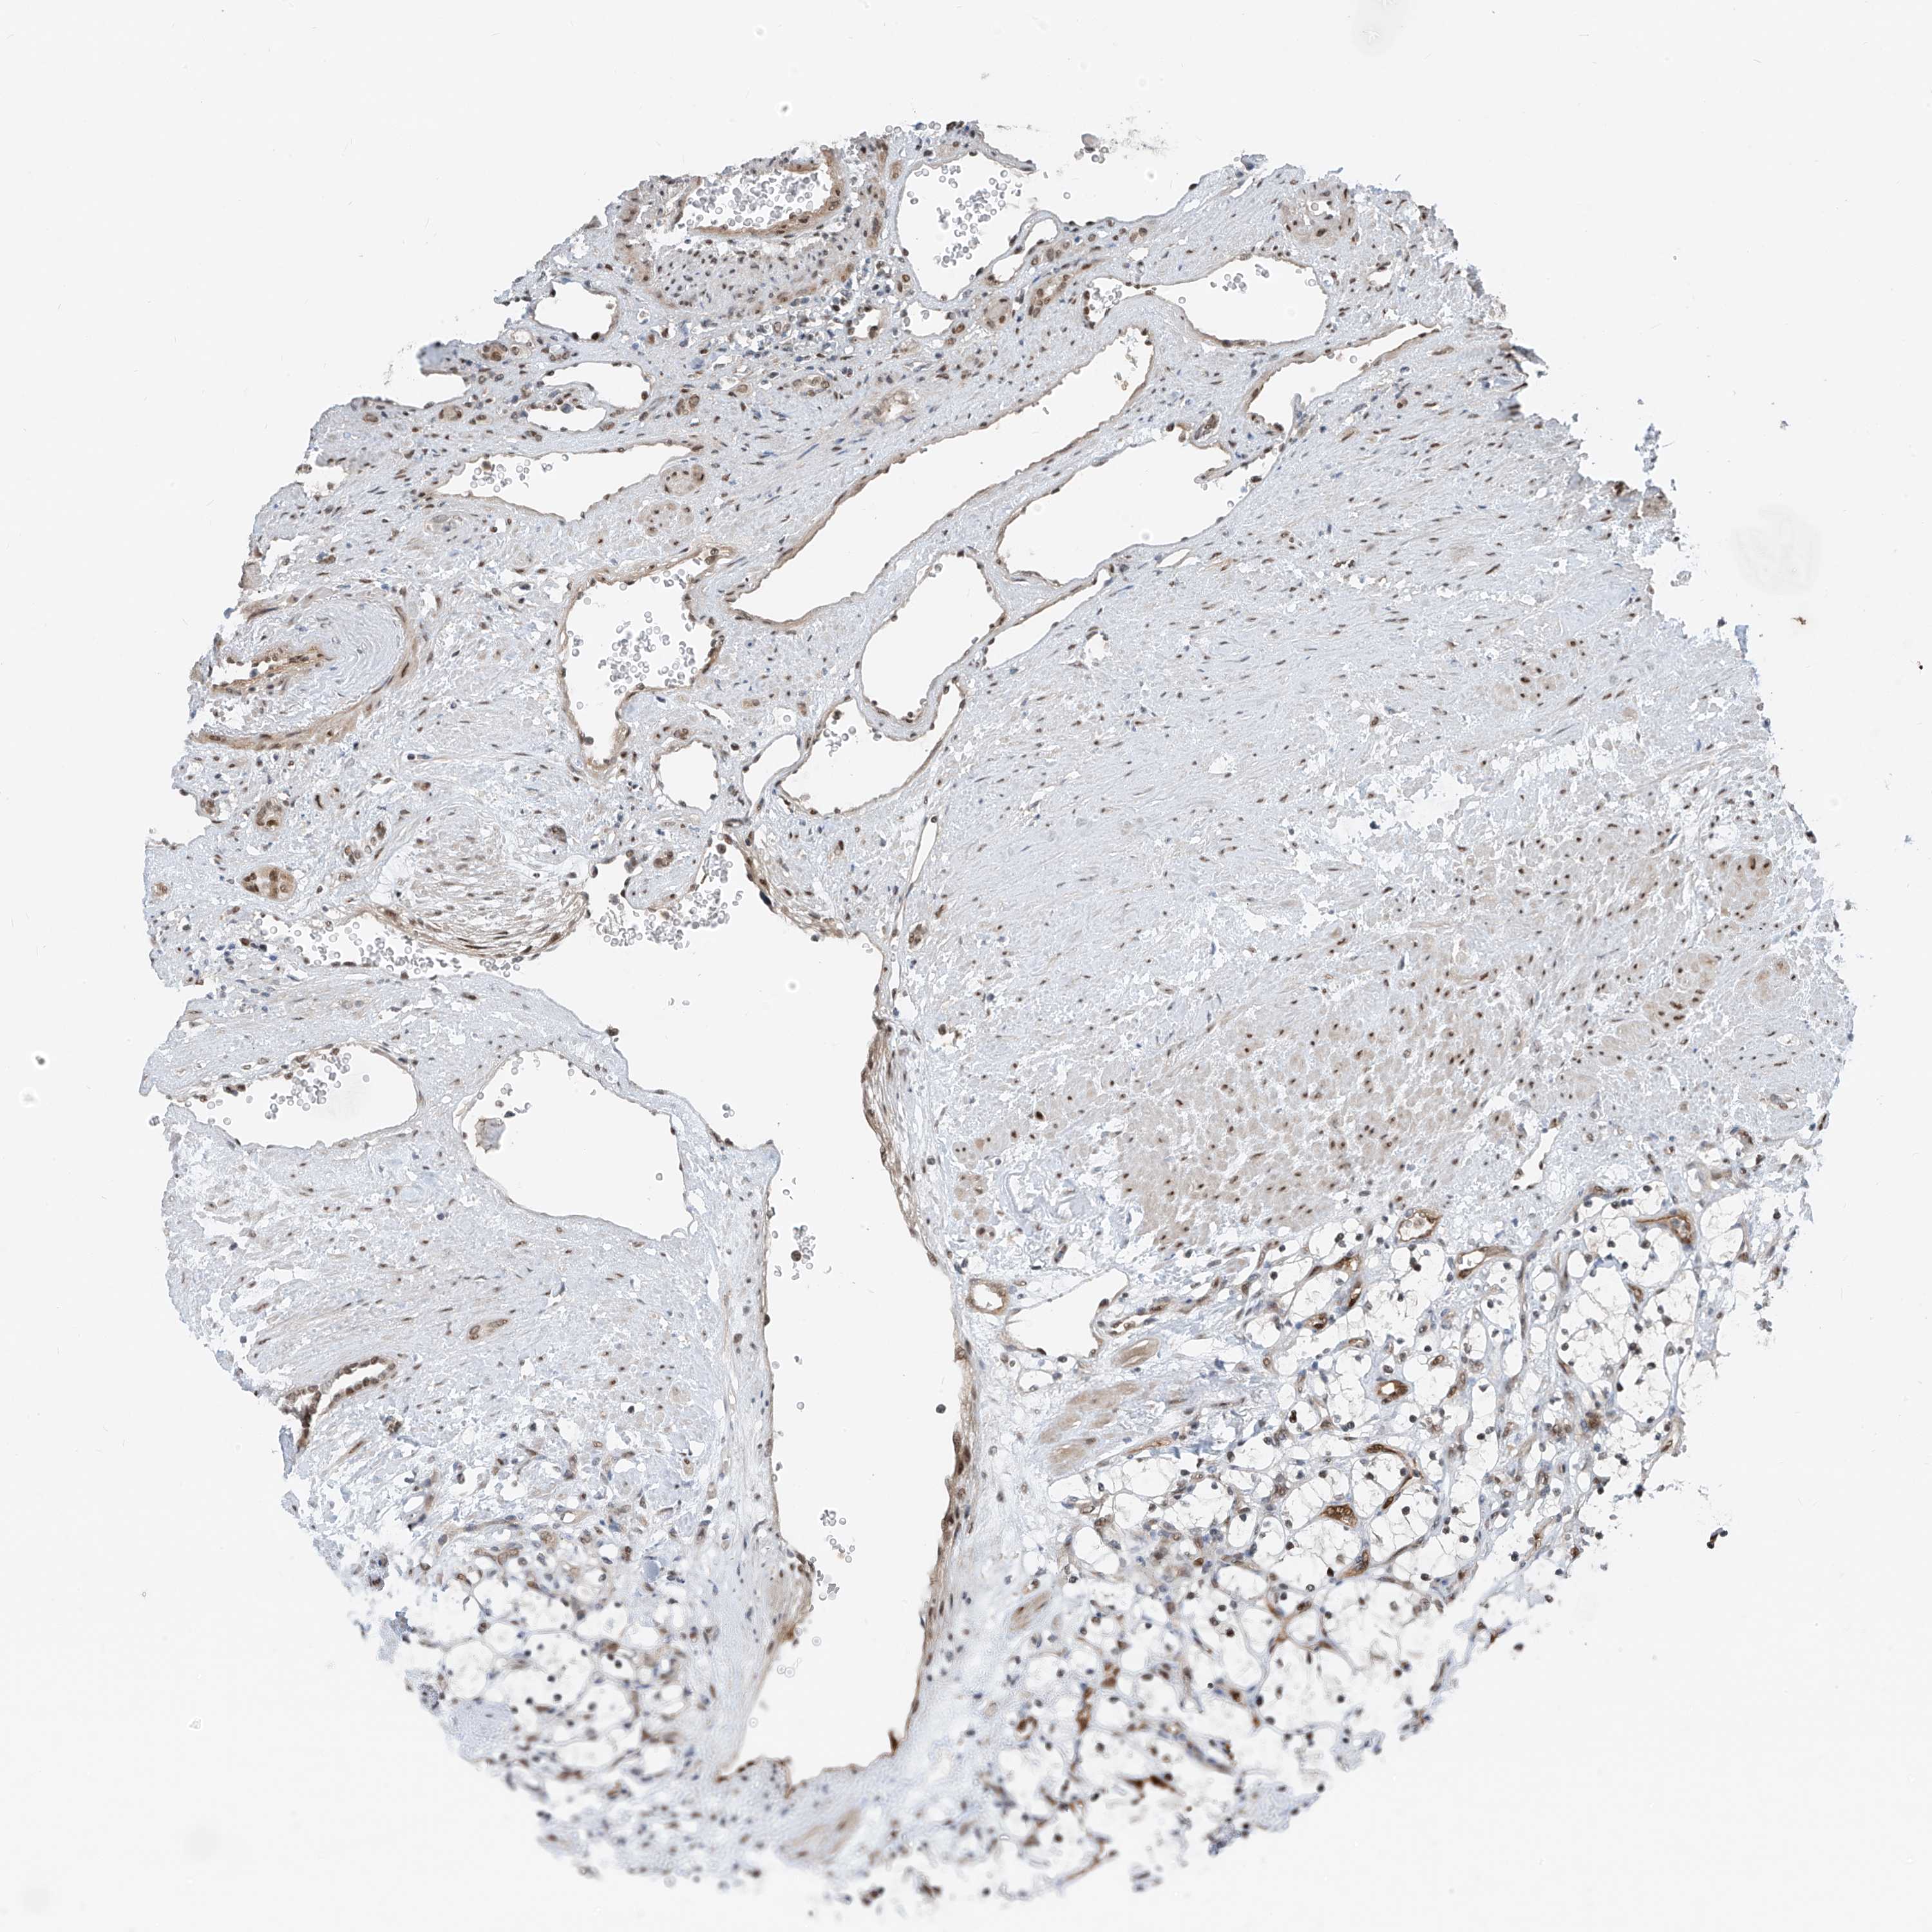

KIDNEY RENAL CLEAR CELL CARCINOMA (VALIDATION) - Interactive survival scatter ploti

The Survival Scatter plot shows the clinical status (i.e. dead or alive) for all individuals in the patient cohort, based on the same data that underlies the corresponding Kaplan-Meier plots. Patients that are alive at last time for follow-up are shown in blue and patients who have died during the study are shown in red.

The x-axis shows the expression levels (FPKM) of the investigated gene in the tumor tissue at the time of diagnosis. The y-axis shows the follow-up time after diagnosis (years). Both axes are complimented with kernel density curves demonstrating the data density over the axes. The top density plot shows the expression levels (FPKM) distribution among dead (red) and alive patients (blue). The right density plot shows the data density of the survived years of dead patients with high and low expression levels respectively, stratified using the cutoff indicated by the vertical dashed line through the Survival Scatter plot. This cutoff is automatically defined based on the FPKM cutoff that minimizes the p-score. The cutoff can be changed by dragging the vertical line or by entering a cutoff value in the square labeled "Current cut-off".

Under the Survival Scatter plot the p-score landscape (black curve; left axis) is shown together with dead median separation (red curve; right axis). Dead median separation is the difference in median mRNA expression between patients who have died with high and low expression, respectively. It is calculated as follows: median FPKM expression of dead patients with high expression - median FPKM expression of dead patients with low expression. This is intended to aid the user in visually exploring custom cutoffs and the associated p-scores and dead median separation.

Individual patient data is displayed and can be filtered by clicking on one or more of the category buttons on the top of the page. Categories describing expression level and patient information include: high, low, alive, dead, female, male and tumor stages. The scale of the x-axis can be toggled between linear and log-scale by clicking on the "x log" button. Mouse-over function shows TCGA ID, patient information and mRNA expression (FPKM) for each patient.

& Survival analysisi

Kaplan-Meier plots summarize results from analysis of correlation between mRNA expression level and patient survival. Patients were divided based on level of expression into one of the two groups "low" (under cut off) or "high" (over cut off). X-axis shows time for survival (years) and y-axis shows the probability of survival, where 1.0 corresponds to 100 percent.

RBP7 is validated prognostic, high expression is favorable in Kidney Renal Clear Cell Carcinoma (validation)

Best expression cut offi

Based on the FPKM value of each gene, patients were classified into two groups and association between prognosis (survival) and gene expression (FPKM) was examined. The best expression cut-off refers the FPKM value that yields maximal difference with regard to survival between the two groups at the lowest log-rank P-value. Best expression cut-off was selected based on survival analysis .

When clicking on this number, the vertical dashed line indicating cut-off, the interactive survival plot, and the Kaplan-Meier curve will be adjusted to show results based on the best expression cut-off.

: 43.39

Average pTPM 64.7

Number of samples 100